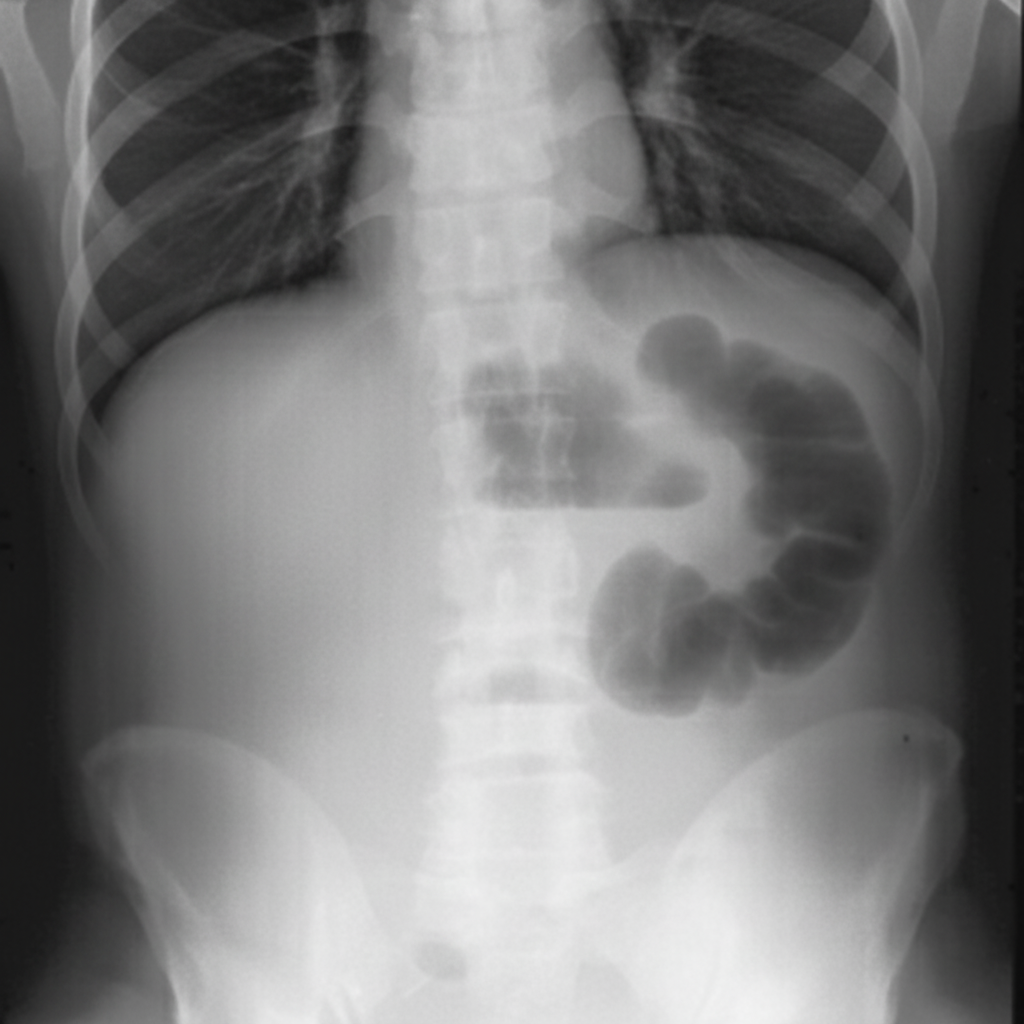

Explanation: ***Paralytic ileus*** - Characterized by **generalized bowel dilatation** with **gas-filled loops** throughout the small and large intestine on abdominal X-ray, without clear transition points. - Presents with **absent or diminished bowel sounds**, abdominal distension, and **delayed passage of gas and stool** due to impaired intestinal motility. *Hyperkalemia* - Primarily causes **cardiac arrhythmias** and **muscle weakness**, not the generalized bowel dilatation pattern seen on imaging. - While severe hyperkalemia can contribute to **ileus**, it's not the primary radiological diagnosis based on the bowel gas pattern. *Acute intestinal obstruction* - Shows **localized bowel dilatation** proximal to the obstruction with a clear **transition zone** and **air-fluid levels** in a step-ladder pattern. - Typically presents with **high-pitched bowel sounds** and **cramping abdominal pain**, contrasting with the quiet abdomen of paralytic ileus. *Malnutrition* - Causes **generalized weakness** and **delayed wound healing** but doesn't produce the characteristic bowel gas distribution pattern. - While malnutrition can predispose to **delayed gastric emptying**, it doesn't directly cause the radiological findings of paralytic ileus.